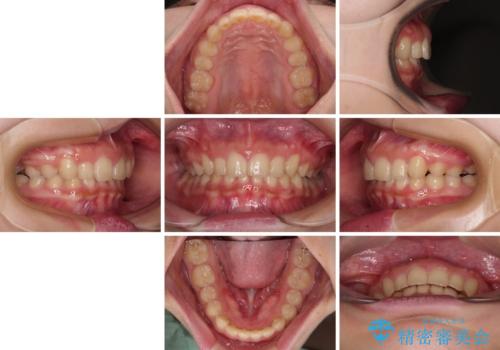

飛び出した前歯をインビザラインですっきりと

- 20代女性

- 矯正装置

- インビザライン

- 深い咬み合わせと上顎前歯の突出感を気にして来院された患者様です。

正面や横からの写真ではきれいに治っており、患者様は大変満足のいく仕上がりとなりましたが、深い咬み合わせの改善は不十分で、奥歯の咬み合わせも改善させることができませんでした。